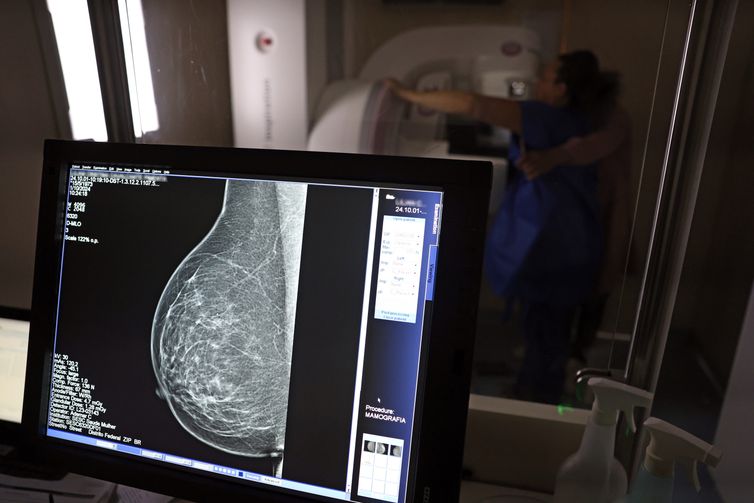

Falta de acesso a mamógrafos limita prevenção do câncer de mama

Atlas da Radiologia mostra que país tem baixa cobertura de mamografias, 24%. O ideal, recomendado pela OMS, é de 70%.

© José Cruz/Agência Brasil

No mês de conscientização sobre o câncer de mama, um relatório destaca a importância de acesso igualitário ao rastreamento e tratamento da doença. Segundo o Atlas da Radiologia no Brasil, do Colégio Brasileiro de Radiologia e Diagnóstico por Imagem (CBR), o acesso aos mamógrafos ainda é um desafio.

O país tem 6.826 equipamentos registrados, sendo 96% em funcionamento. Metade deles está disponível no Sistema Único de Saúde (SUS), responsável por atender 75% da população. Isso equivale a 2,13 mamógrafos por 100 mil habitantes dependentes do SUS.

Na saúde suplementar, que cobre 25% da população, o cenário é mais favorável: 6,54 aparelhos por 100 mil beneficiárias, quase o triplo da rede pública. O Acre exemplifica essa disparidade — são 35,38 mamógrafos por 100 mil habitantes na rede privada, contra 0,84 no SUS.

Há disparidades regionais. Roraima tem a menor proporção (1,53 por 100 mil), seguida do Ceará (2,23) e Pará (2,25). A Paraíba lidera o ranking (4,32), à frente do Distrito Federal (4,26) e do Rio de Janeiro (3,93).

O Brasil tem uma cobertura muito baixa de mamografias: 24%. O ideal recomendado pela Organização Mundial da Saúde é de 70%. Mesmo em lugares como o estado de São Paulo, que tem a maior concentração de mamógrafos do país, a taxa gira em torno de 26%.